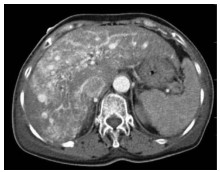

Consensus on imaging techniques and diagnostic criteria for hepatitis B virus related early hepatocellular carcinoma

Radiology of Infection Sub-branch, Radiology Branch, Chinese Medical Association, Committee on Radiology of Infection, Radiology Branch, Chinese Medical Doctor Association, Radiology Committee on Infectious and Inflammatory Disease, Chinese Research Hospital Association, Radiology of Infection Branch, Working and Treating Committee of HIV/AIDS and STD Association, Radiology of Infectious Disease Management Sub-branch, Infectious Disease Management Branch, Hospital Management Association in China, Beijing Imaging Diagnosis and Treatment Technology Innovation Alliance

2021, 37(4): 787-791. DOI: 10.3969/j.issn.1001-5256.2021.04.013

Abstract(1427) HTML (513) PDF (4471KB)(236)

Abstract:

The pathological diagnostic criteria for early hepatocellular carcinoma(eHCC)have been updated in 2009, but the imaging diagnostic criteria for eHCC have not yet been established by domestic or foreign academic organizations. Promoted by Radiology of Infection Sub-branch, Radiology Branch, Chinese Medical Association, associating with Committee on Radiology of Infection, Radiology Branch, Chinese Medical Doctor Association; Radiology Committee on Infectious and Inflammatory Disease, Chinese Research Hospital Association; Radiology of Infection Branch, Working and Treating Committee of HIV/AIDS and STD Association; Radiology of Infectious Disease Management Sub-branch, Infectious Disease Management Branch, Hospital Management Association in China; Beijing Imaging Diagnosis and Treatment Technology Innovation Alliance, this consensus was formed under the efforts of more than 40 experts from more than 10 domestic provinces and cities, so as to help related professional doctors in diagnosis of eHCC.